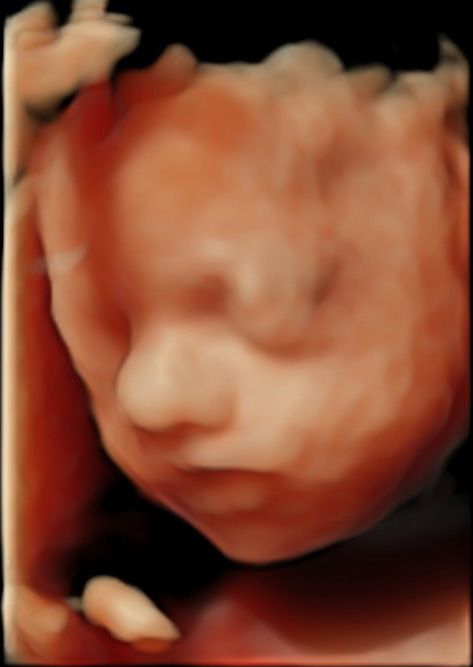

De eerste echo zal plaatsvinden als je ongeveer 8 weken zwanger bent. Tijdens deze echo wordt gekeken of de zwangerschap intact is en wordt de zwangerschapsduur bevestigd. Tijdens deze echo wordt er ook gekeken of er sprake is van een eenling -of meerlingzwangerschap. Bij echo’s voor 10 weken wordt vaak een inwendige echo gemaakt, omdat de baarmoeder bij deze termijn nog te klein is om via de buikwand in beeld te krijgen. Een inwendige echo geeft de meest scherpe beelden en foto’s bij een jonge zwangerschap. Ook in een latere periode kan er toch besloten worden om over te gaan op een inwendige echo indien de uitwendige echo geen goede beeldkwaliteit geeft.

De tweede echo volgt bij 10-11 weken zwangerschap. Aan de hand van deze echo wordt de uitgerekende datum bepaald.

De 20 wekenecho wordt ook wel structureel echoscopisch onderzoek genoemd. Hoofddoel van de 20 wekenecho is onderzoek naar de aanwezigheid van een open rug of een open schedel bij het kind. Bij deze echo wordt uitgebreid gekeken naar de ontwikkeling van de organen van het kind, zoals het hart, de maag, darmen, nieren en de blaas. Verder wordt gekeken of het kind goed groeit en of er voldoende vruchtwater is. De echo kan plaats vinden tussen de 18 en 21 weken zwangerschap. De beste termijn is tussen de 19 en 20 weken.